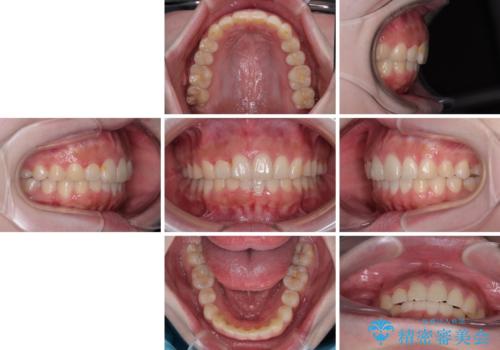

前歯のデコボコをインビザラインできれいに整える

前歯の捻れを改善するとともに、口元が少しでも引っ込むように治療計画を立て、仕上げることができました。

- 2年6ヶ月

- 5-10回